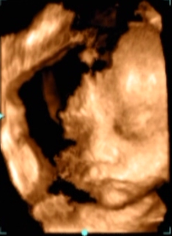

初めて4Dで診てもらいました!あまりにパパそっくりの男の子で思わず笑っちゃいました(^o^)/

旦那ちゃんにソックリ!

口を開けてあくびをしたり笑ったり、いろんな表情をしてくれました★

鼻や輪郭は旦那さんにそっくり♪とってもかわいらしい男の子です。胎動も激しく、元気に成長している様子…